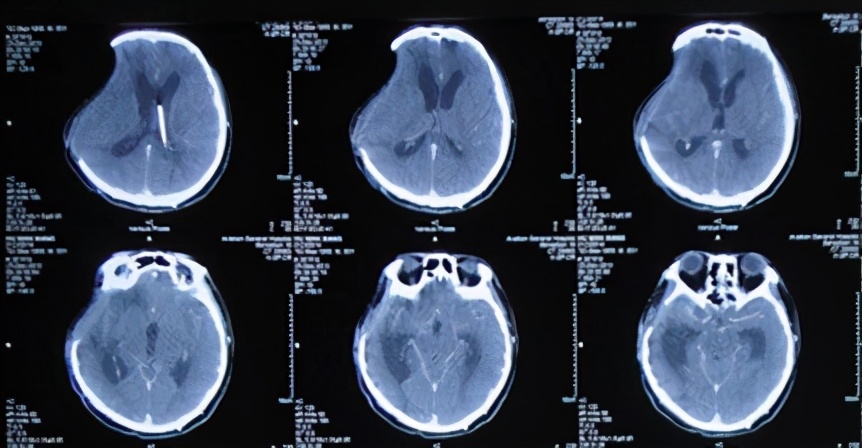

出院休养2周后,患者出现反应及肢体活动均渐进性迟缓的表现,继续在家观察半个月之后,于2014年2月19日,患者为解决颅骨缺损而再次来院治疗,此时患者已经不能独自站立,且精神差、嗜睡(图-20),当天行头CT检查:有脑内陷表现(图-21)。

图-20:2014年2月19日

图-21:2014年2月19日头CT

在2014年2月25日即第2次住院第6天时(开颅术后第163天),患者接受了颅骨缺损的修补术,术后当天查头CT:颅骨修补术后改变(图-22)。

图-22:2014年2月25日头CT

在颅骨修补术后第2天,患者即有所改善,僵硬的左侧肢体活动较术前灵活。于2014年3月3日即颅骨修补术后第6天(开颅术后第169天),复查头CT:硬膜外积液有所吸收,脑皮质受压较前减轻(图-23),并在此次复查头CT后拔除术区硬膜外引流管。

图-23:2014年3月3日头CT

但在拔除术区硬膜外引流管后的2天,患者开始出现嗜睡加重表现。于2014年3月6日即拔除术区硬膜外引流管第3天即颅骨修补术后第9天(开颅术后第172天),再次复查头CT:硬膜外积液(血)增多,中线结构受压移位加重(图-24)。此时患者尚可唤醒,生命征平稳,遂给予继续观察。

图-24:2014年3月6日头CT

2014年3月9日即继续观察3天后即拔除术区硬膜外引流管第6天即颅骨修补术后第12天(开颅术后第175天),患者出现嗜睡状态较前加重(呼喊无应答)并伴双侧瞳孔不等大,夜间复查头颅CT:右侧硬膜外积液较前增大伴中线左侧偏移(图-25),给予甘露醇250ml静脉点滴后意识稍改善,可唤醒。

图-25:2014年3月9日头CT

但次日晨起即2014年3月10日即拔除术区硬膜外引流管第7天即颅骨修补术后第13天(开颅术后第176天),患者再次嗜睡加重,呼喊无应答,强刺痛可反应。遂给予患者床旁抽吸硬膜外积液,量约40ml,抽吸后患者可自动睁眼(图-26)。留取部分穿刺液行细菌培养,并给予穿刺部位留置负压吸引持续引流硬膜外积液。

图-26:2014年3月10日抽吸硬膜外积液前、后及次日情况

2014年3月16日即留置硬膜外积液持续引流第6天即颅骨修补术后第19天(开颅术后第182天),复查头颅CT:硬膜外积气、液及血均较前缩小,中线受压移位减轻(图-27)。

图-27:2014年3月16日头CT

2014年3月24日即留置硬膜外积液持续引流第14天即颅骨修补术后第27天(开颅术后第190天),复查头CT:硬膜外积液及中线移位均再次减轻(图-28)。并在此次复查CT后拔除硬膜外引流管,继续给予静脉抗感染治疗。

图-28:2014年3月24日头CT

此后又分别于2014年3月31日(图-29)、2014年4月8日(图-30)、2014年5月5日(图-31)复查头CT显示硬膜外积液逐渐吸收并基本消失。且此期间患者状态也明显改善,已可以下床活动(图-32)。

图-29:2014年3月31日头CT

图-30:2014年4月8日头CT

图-31:2014年5月5日头CT

2014年5月14日即颅骨修补术后第78天(开颅术后第241天),患者复查头CT:右侧硬膜外积液完全吸收(图-33),并在2天后即2014年5月16日出院,出院时:行走需搀扶,仍存在反应迟钝和肢体活动功能的不足(图-34)。

图-33:2014年5月14日头CT